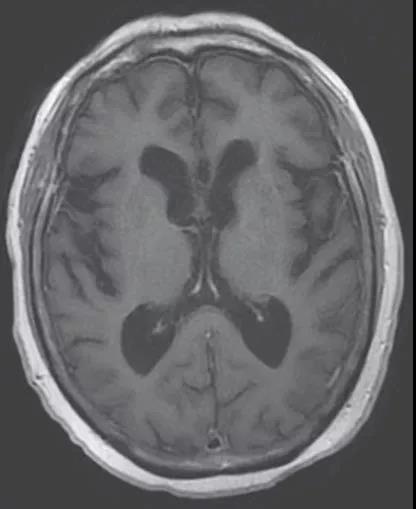

70岁,男性。长期情绪低落,步态不稳,尿失禁。该患者的MRI如下:

因为怀疑正压性脑积水,随后行腰穿脑脊液放液试验,下面的视频是腰穿脑脊液放液前后患者的变化:

因为放液试验有效,随后进行了脑室分流手术,手术后症状明显改善。